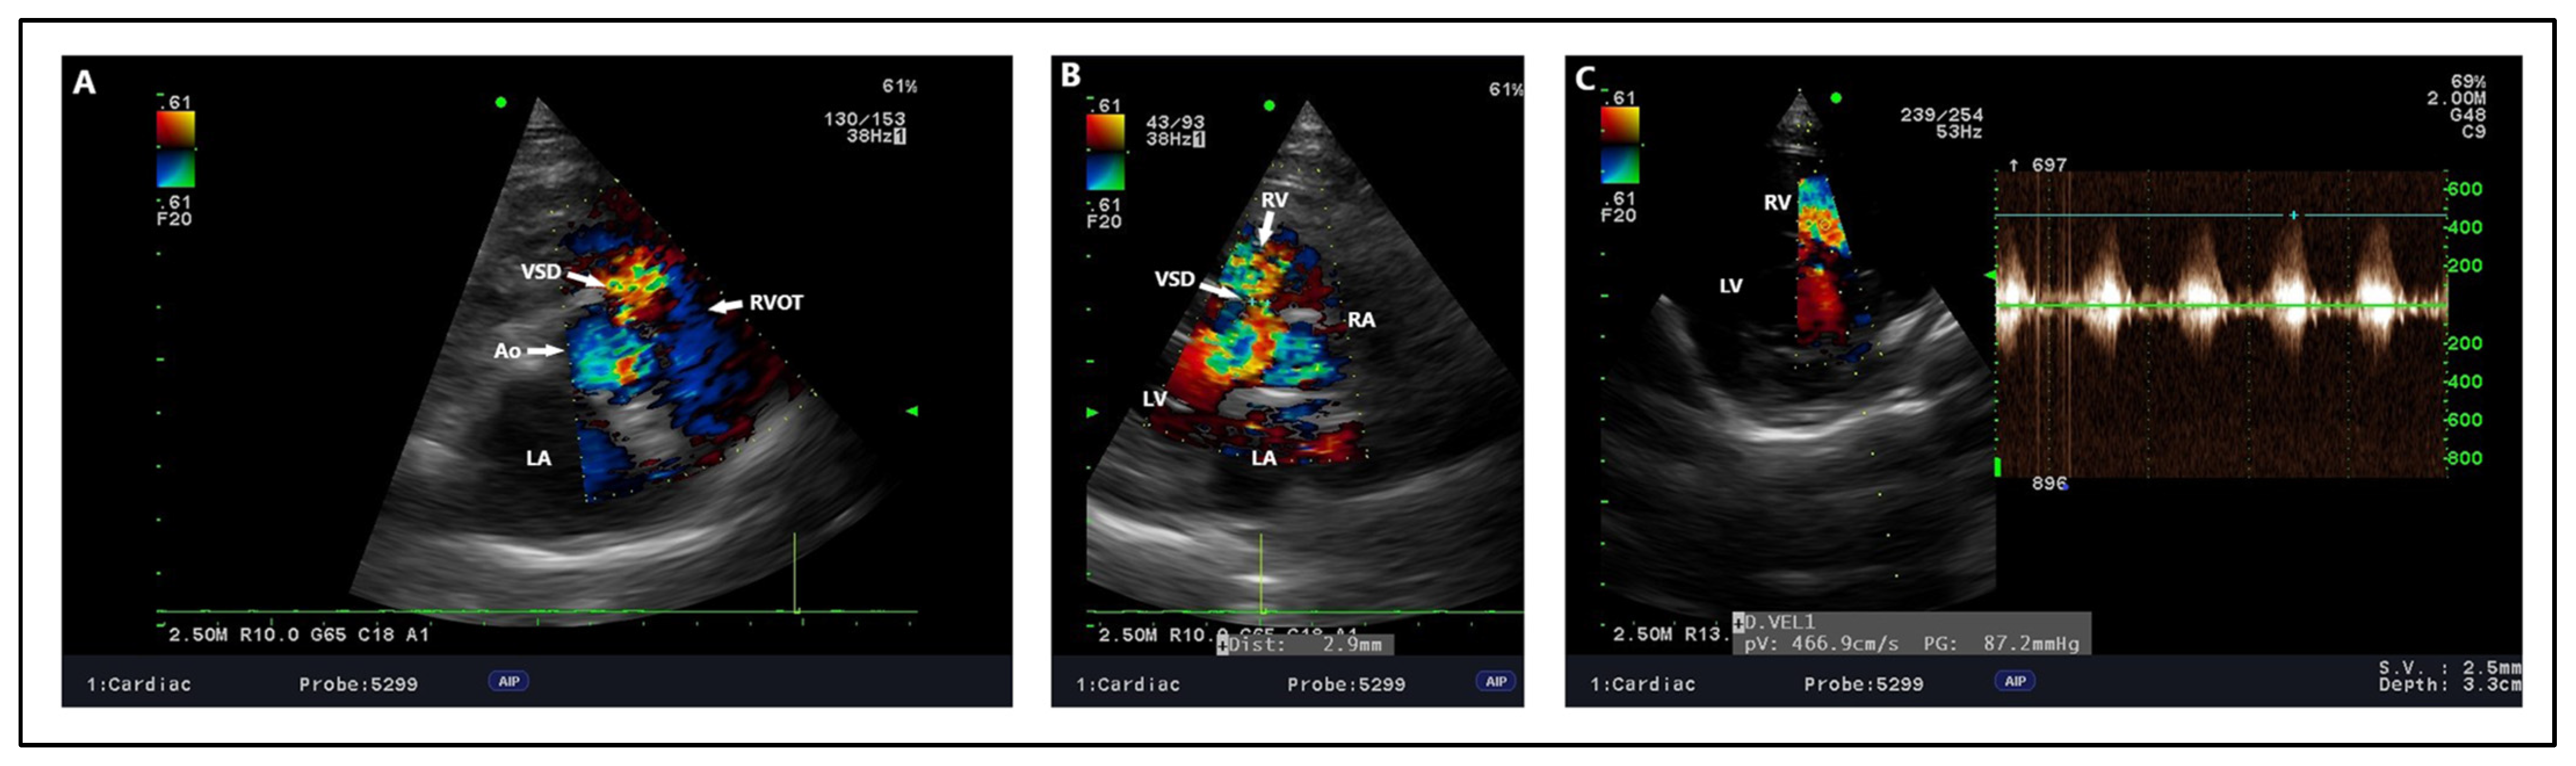

| [13] | English Sheepdog | 12 | IV/VI right-sided holosystolic murmur, reduced exercise capability | Perimembranous, 6 | 4.8 m/s | Percutaneous transcatheter closure (Amplatzer occluder) | Qp:Qs: 1.76, EDVI—215 mL/m2, L-to-R shunt, Pressure gradient 92.2 mmHg | No residual flow through the device | Mild cardiomegaly with over-circulation of pulmonary vasculature, pulmonary venous congestion | VPCs—isolated ventricular premature beats, ECG after treatment was normal | Clinically normal after 1 month |

4.2. Echocardiography, Radiography, ECG Findings